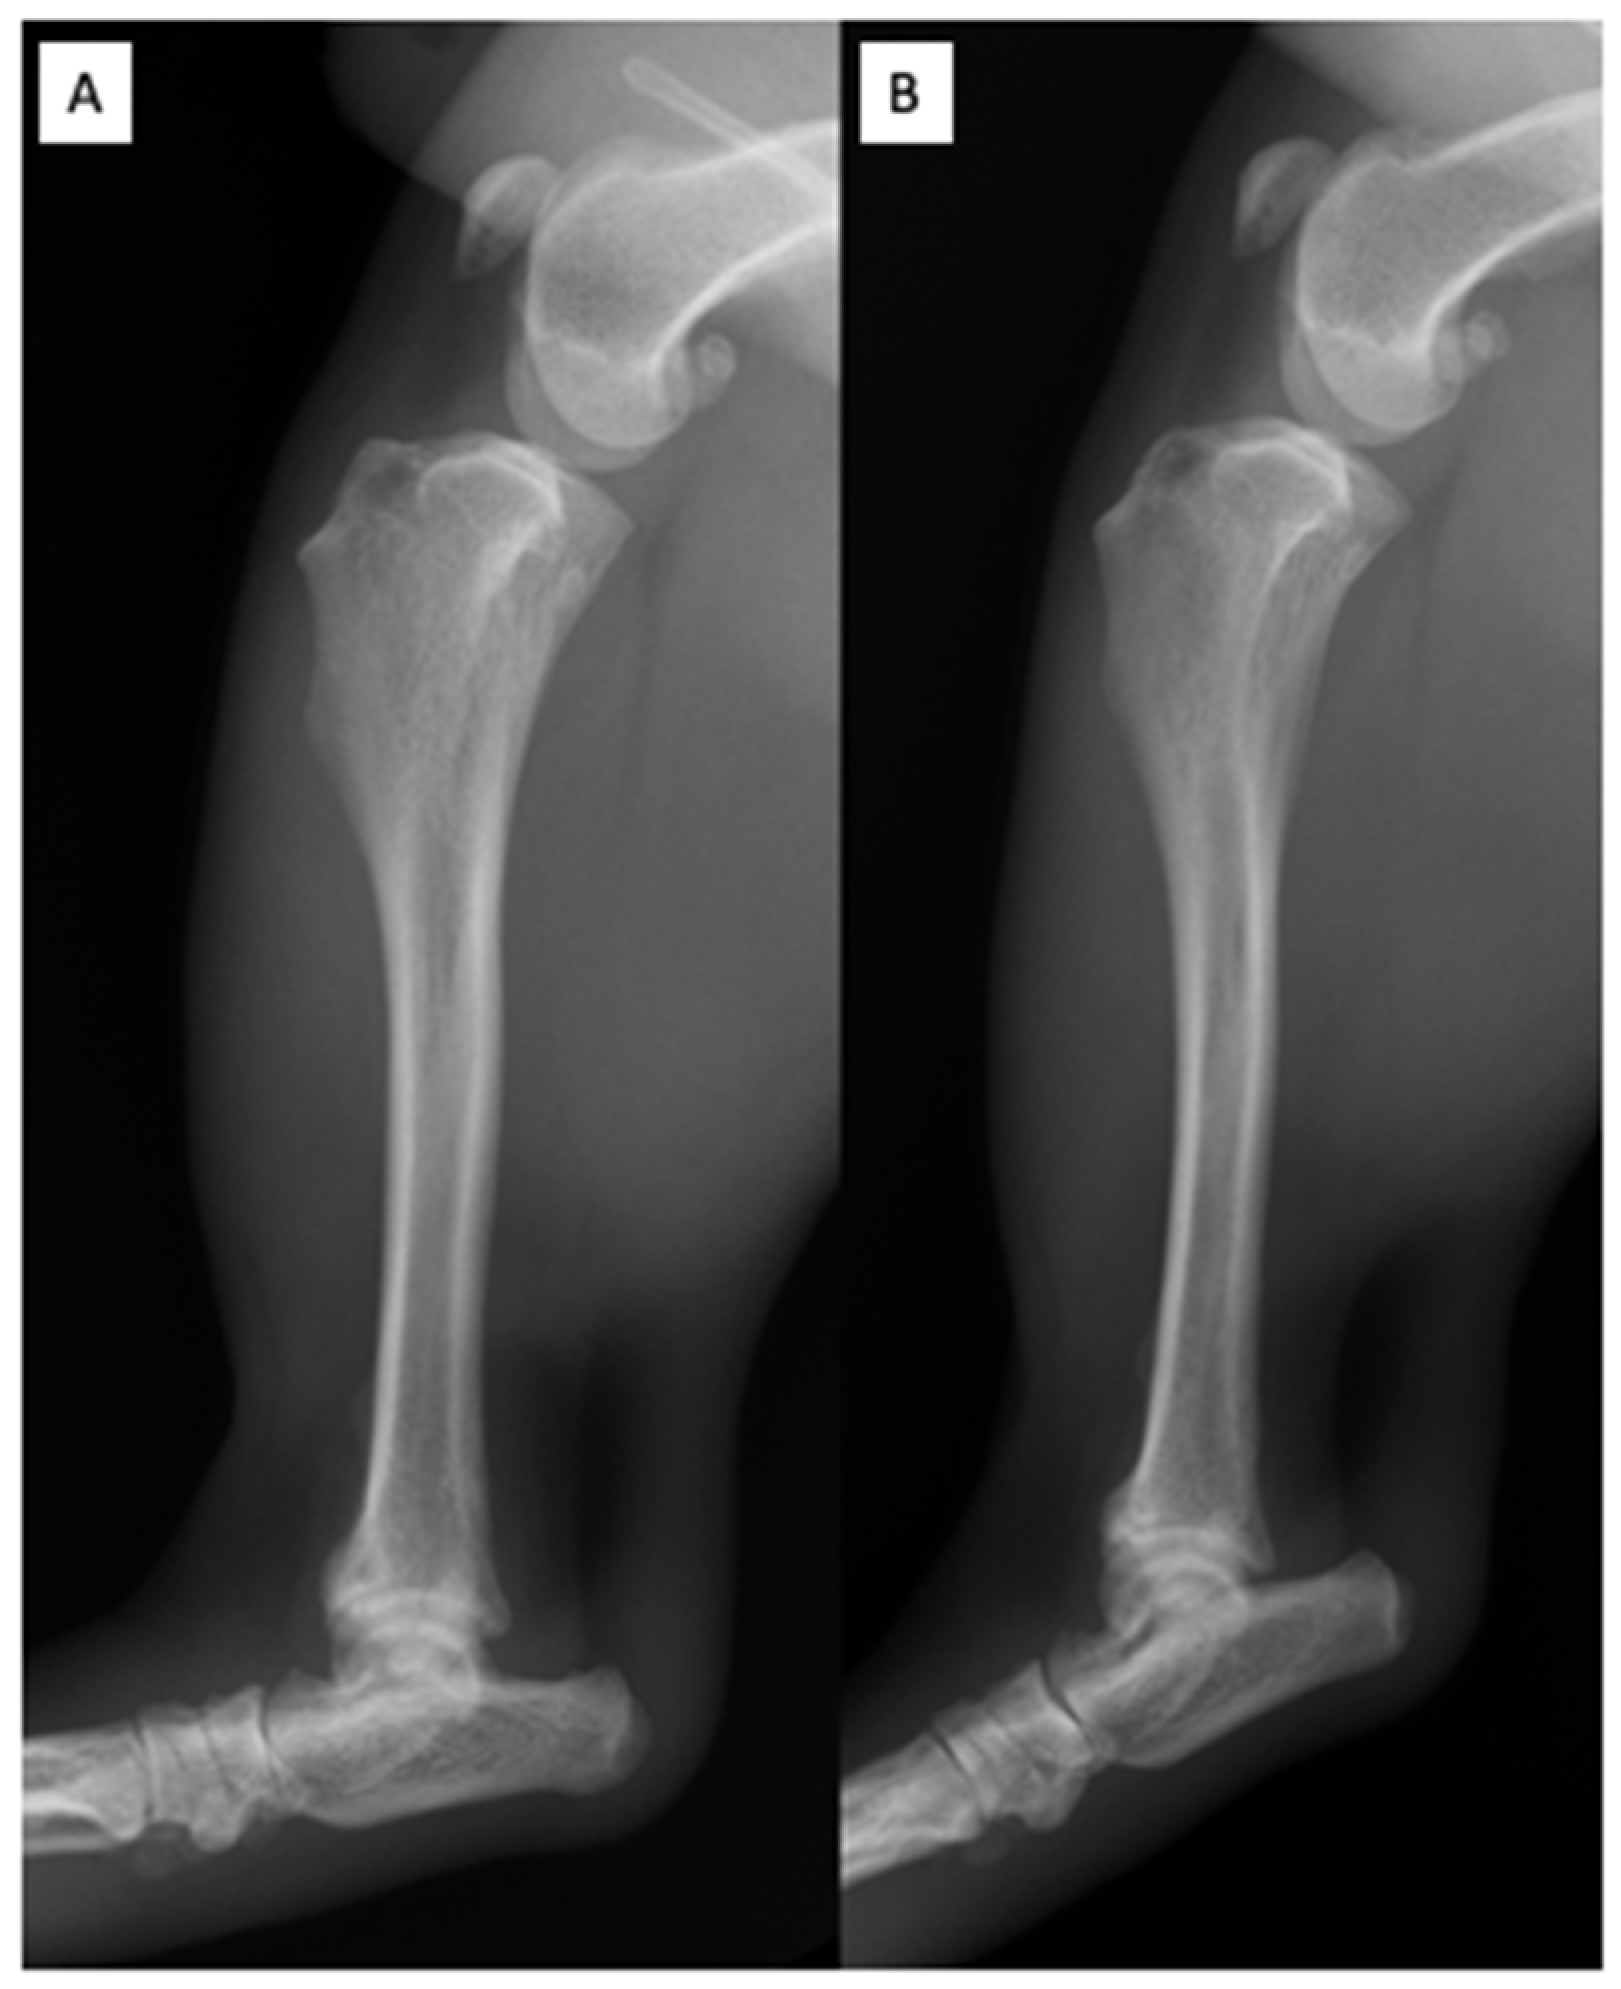

2.2. Orthopedic Examination and Radiological Findings